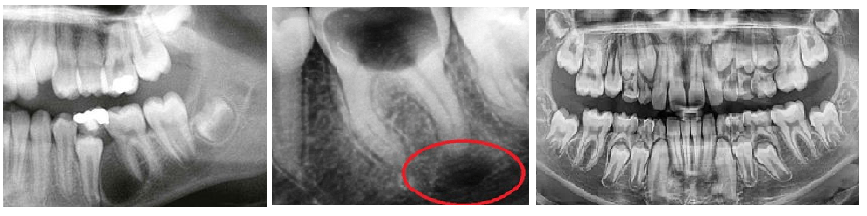

Гранулемы редко превышают 1 см в диаметре. Небольшие гранулемы можно различить только при рентгенологическом исследовании, ортопантомограмме или компьютерной томографии.

Уточнить диагноз помогут инструментальные обследования:

- рентген-снимок;

- радиовизиография;

- компьютерная томография. На рентгене гранулема выглядит как округлое затемненное пятно с четкими контурами.

Гранулему дифференцируют с кистами, новообразованиями, в том числе костной опухолью. При необходимости требуются вспомогательные методы обследования.